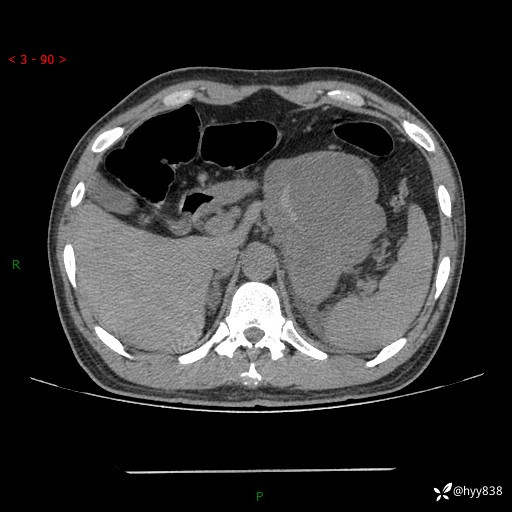

病例39岁/女,左侧腰痛入院。腹腔囊实性肿块,定位、定性---结果公布~

性别:男

年龄:39岁

简要病史:左侧腰痛待查,CT发现腹腔占位

腹部CT平扫+增强